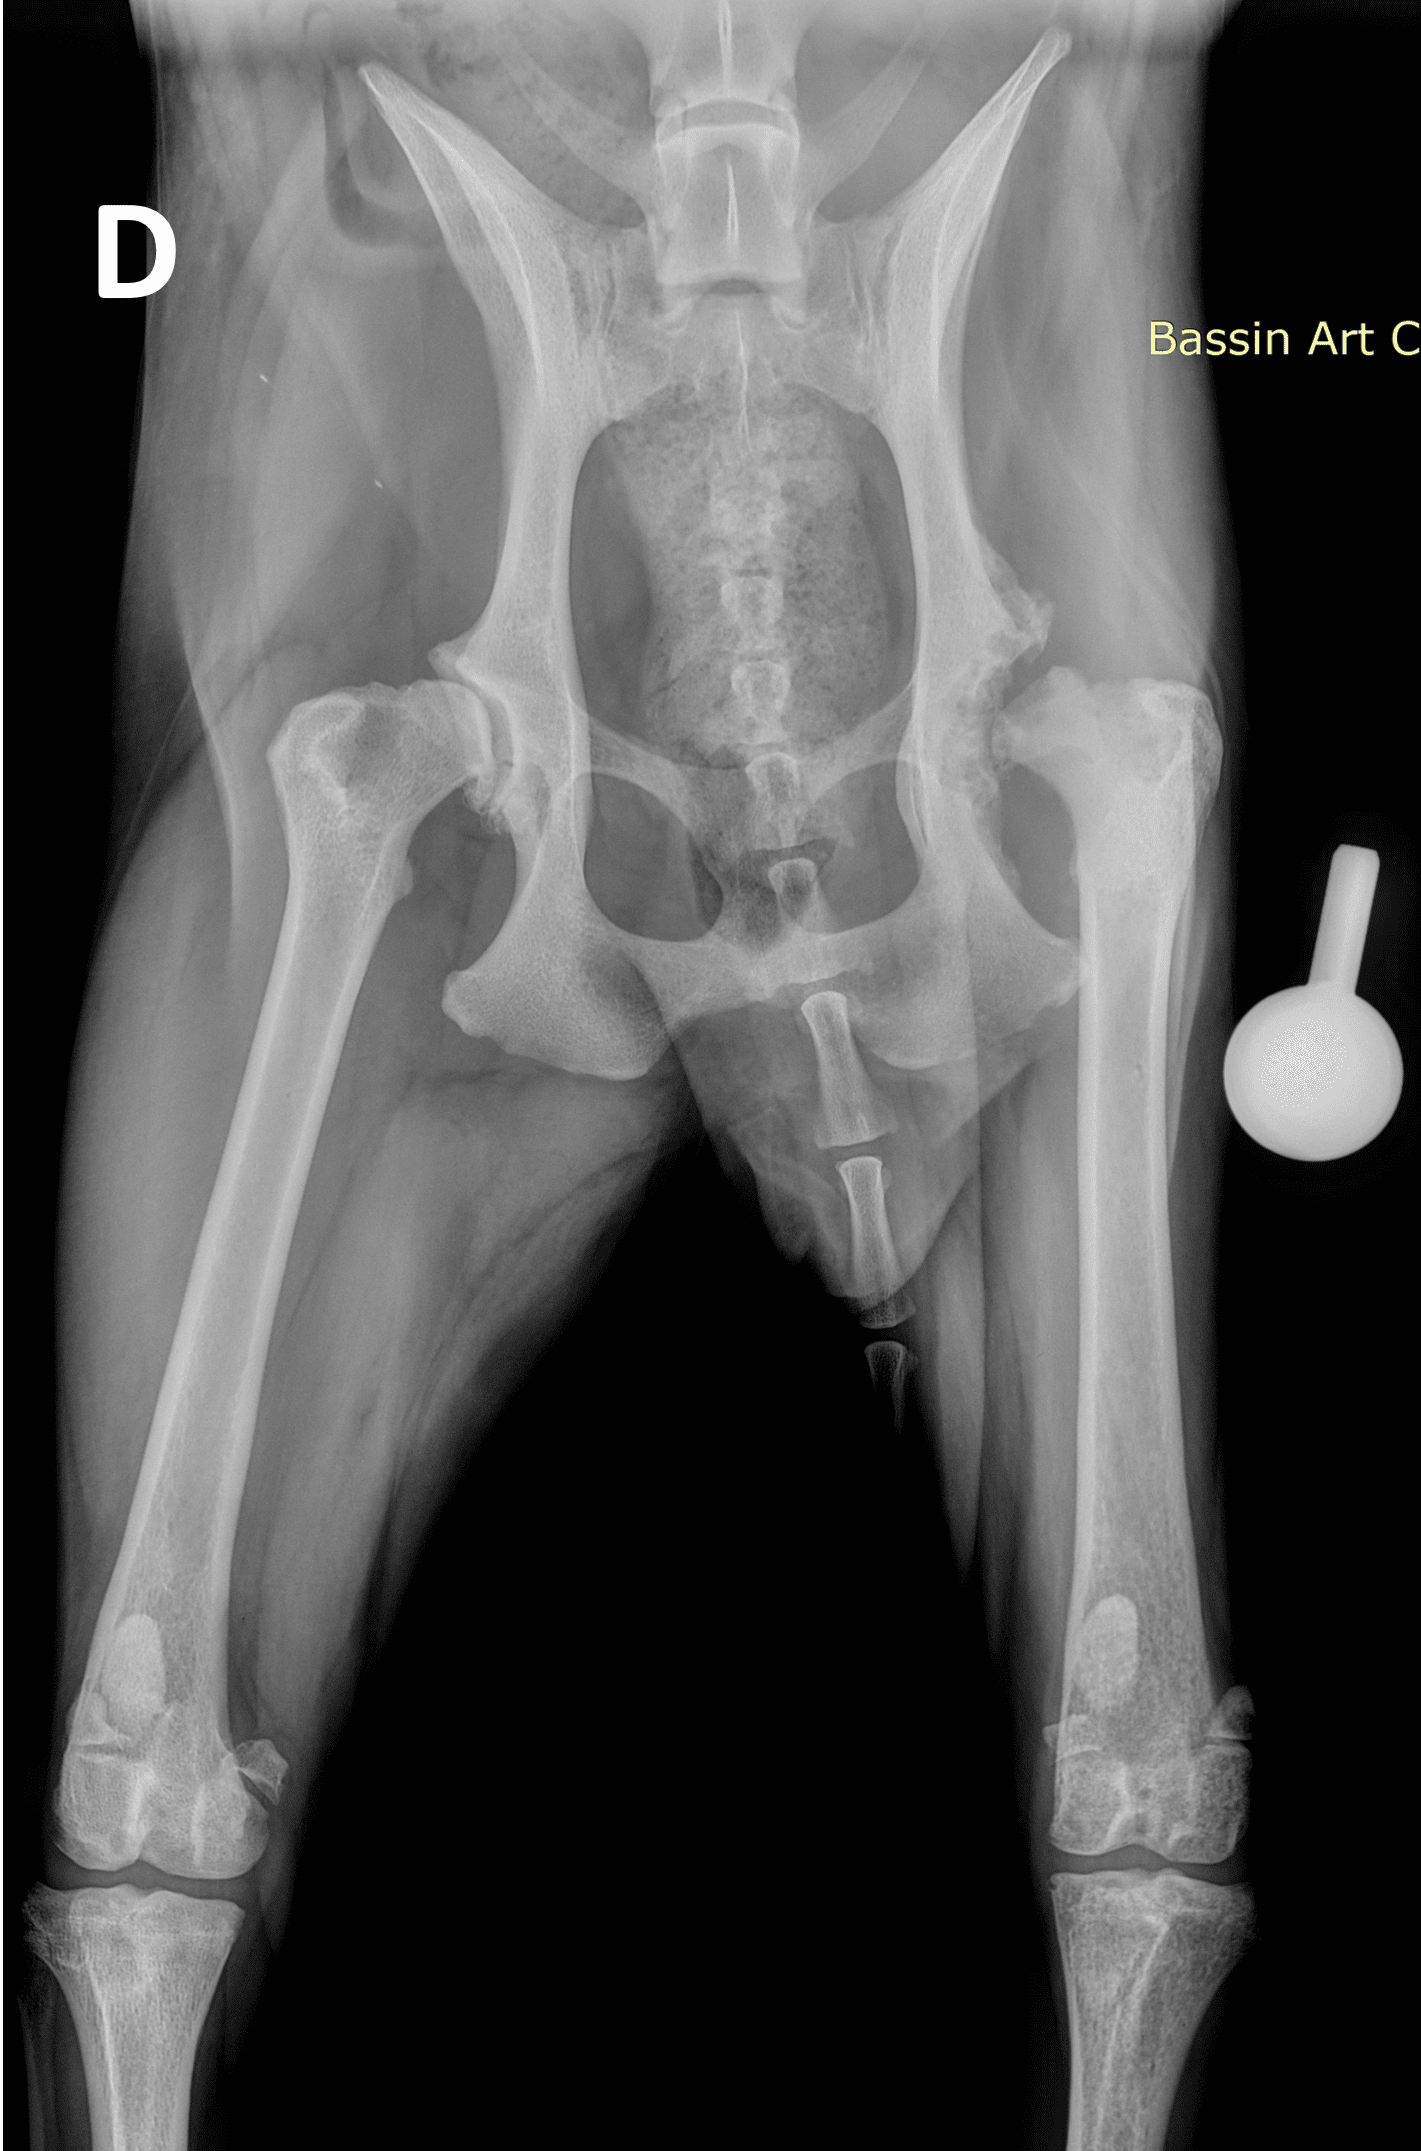

L’articulation de la hanche est exposée, une ostectomie de la tête et du col fémoral permet leur ablation.

Des radiographies de contrôle post-opératoires sont réalisées.

Après la chirurgie, un tissu fibreux se forme dans la région de l’articulation de la hanche, empêchant ainsi le contact entre l’acétabulum contre le fémur créant une pseudo-articulation. La masse musculaire maintient la hanche en place. La patte opérée sera légèrement plus courte qu’en préopératoire.